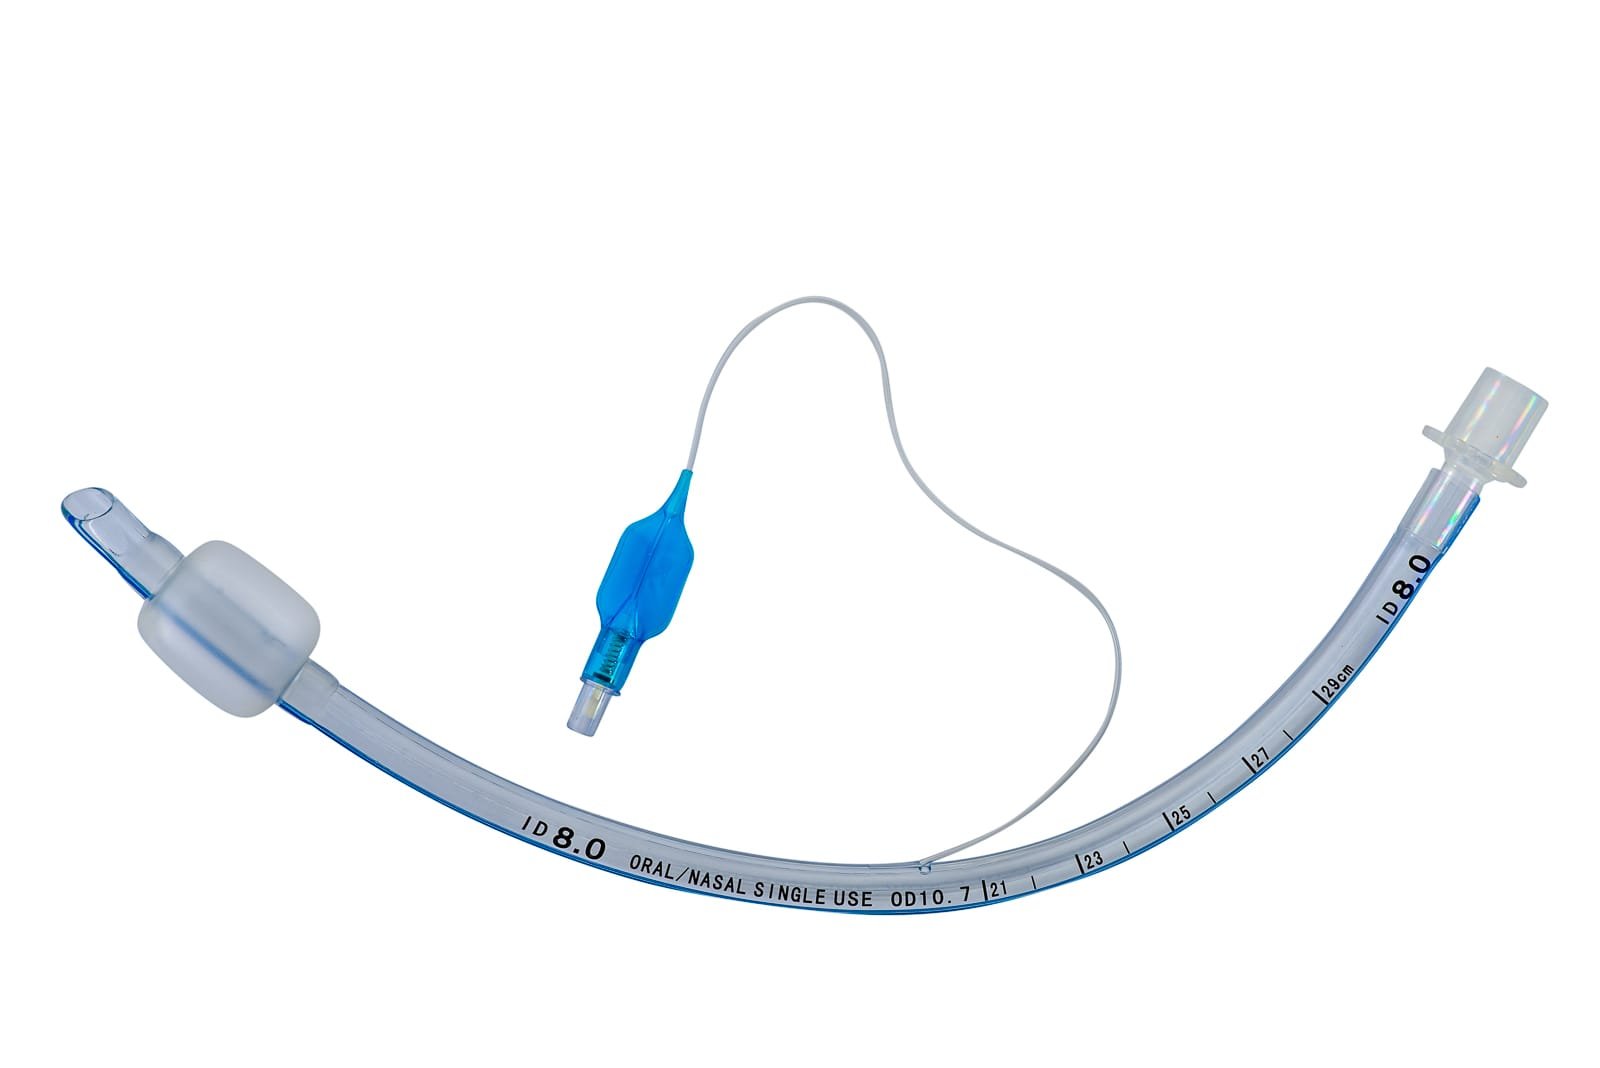

Endotracheal Tube (Cuffed)

Endotracheal Tube (Cuffed)Our ProductsFrom SurgicaveUplode:9 months ago from India